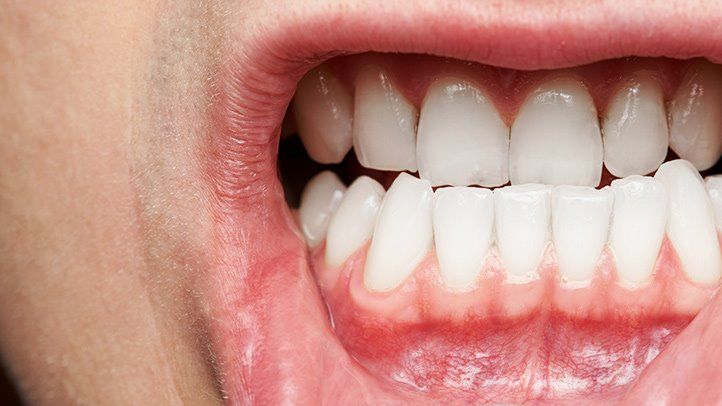

Wisdom teeth are located at the back of the mouth, making them difficult to clean properly. Poor oral hygiene can lead to tooth decay and gum disease in these molars and neighboring teeth.